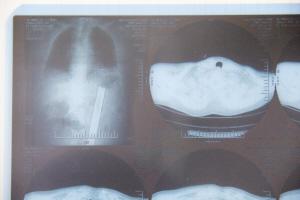

图为医院拍片,红圈处为水管

省医医生经过照片检查,发现老人体内有异物,决定动手术治疗。经过手术,取出异物,发现是一根塑料水管。

记者看到,从老人身体内取出的黑色塑料管,大约有50公分长,管道直径约2厘米,看上去应该是自来水管。

患者女儿告诉记者,从拍的片子来看,这根塑料管藏在父亲的左侧肠道中,一端则留在肛门里,另一端则靠近胃部。因为肛门被塑料管损害,还需要进行手术治疗。